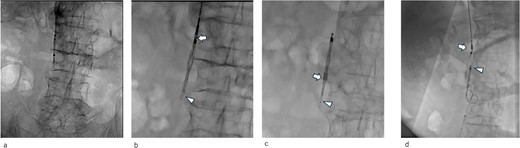

Abdominal X-ray image after the surgery. Two inferior vena cava filters are placed.